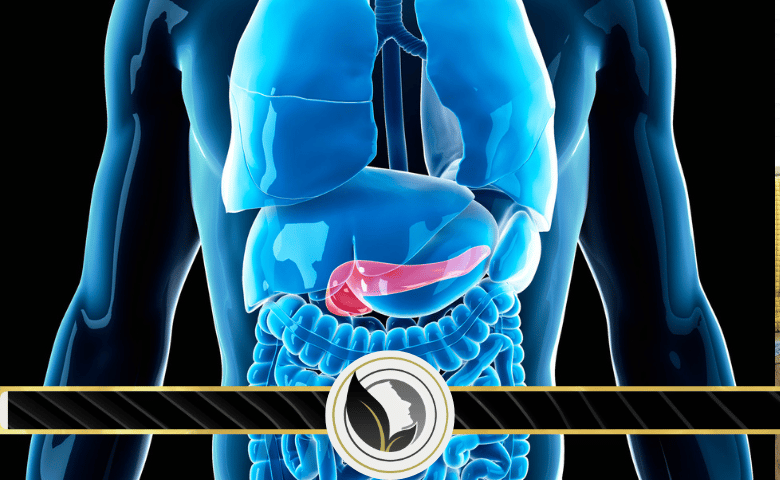

علامات تحذيرية لسرطان البنكرياس

يعتبر سرطان البنكرياس من الأمراض الخطيرة التي لا تتسبب بظهور أعراض في المراحل المبكرة، إلا أن هناك بعض المؤشرات التي يمكن أن تتنبأ بالإصابة به.